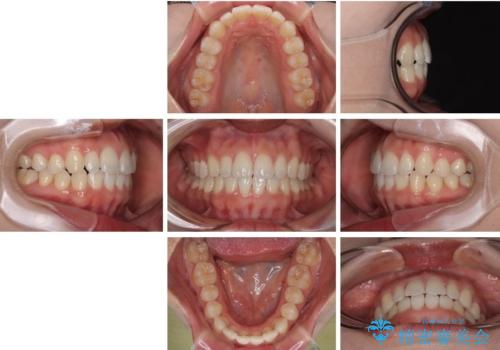

治療終了時

前歯が自然なアーチにきれいに並び、正中(上下の中心線)も整い、咬み合わせも良好です。

側方拡大することで、非抜歯であるにも関わらず前歯が前方に出ることなく、バランスの良い仕上がりとなりました。

「矯正装置が目立たず、思ったより短期間で仕上がりに満足しています。鏡を見るのが毎日楽しみになりました!」とうれしいお言葉をいただきました。